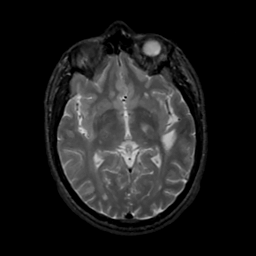

MR Study #8, March 31, 1991 -- Slice #24